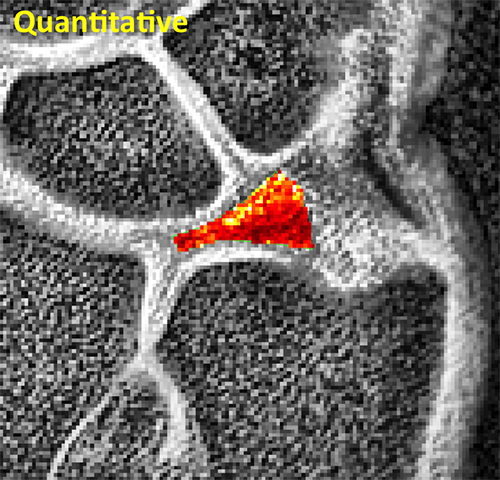

TMJ Quantitative

Quantitative MRI reveals subtle differences in T2 values of the TMJ disc that reflect early changes in its collagen structure.